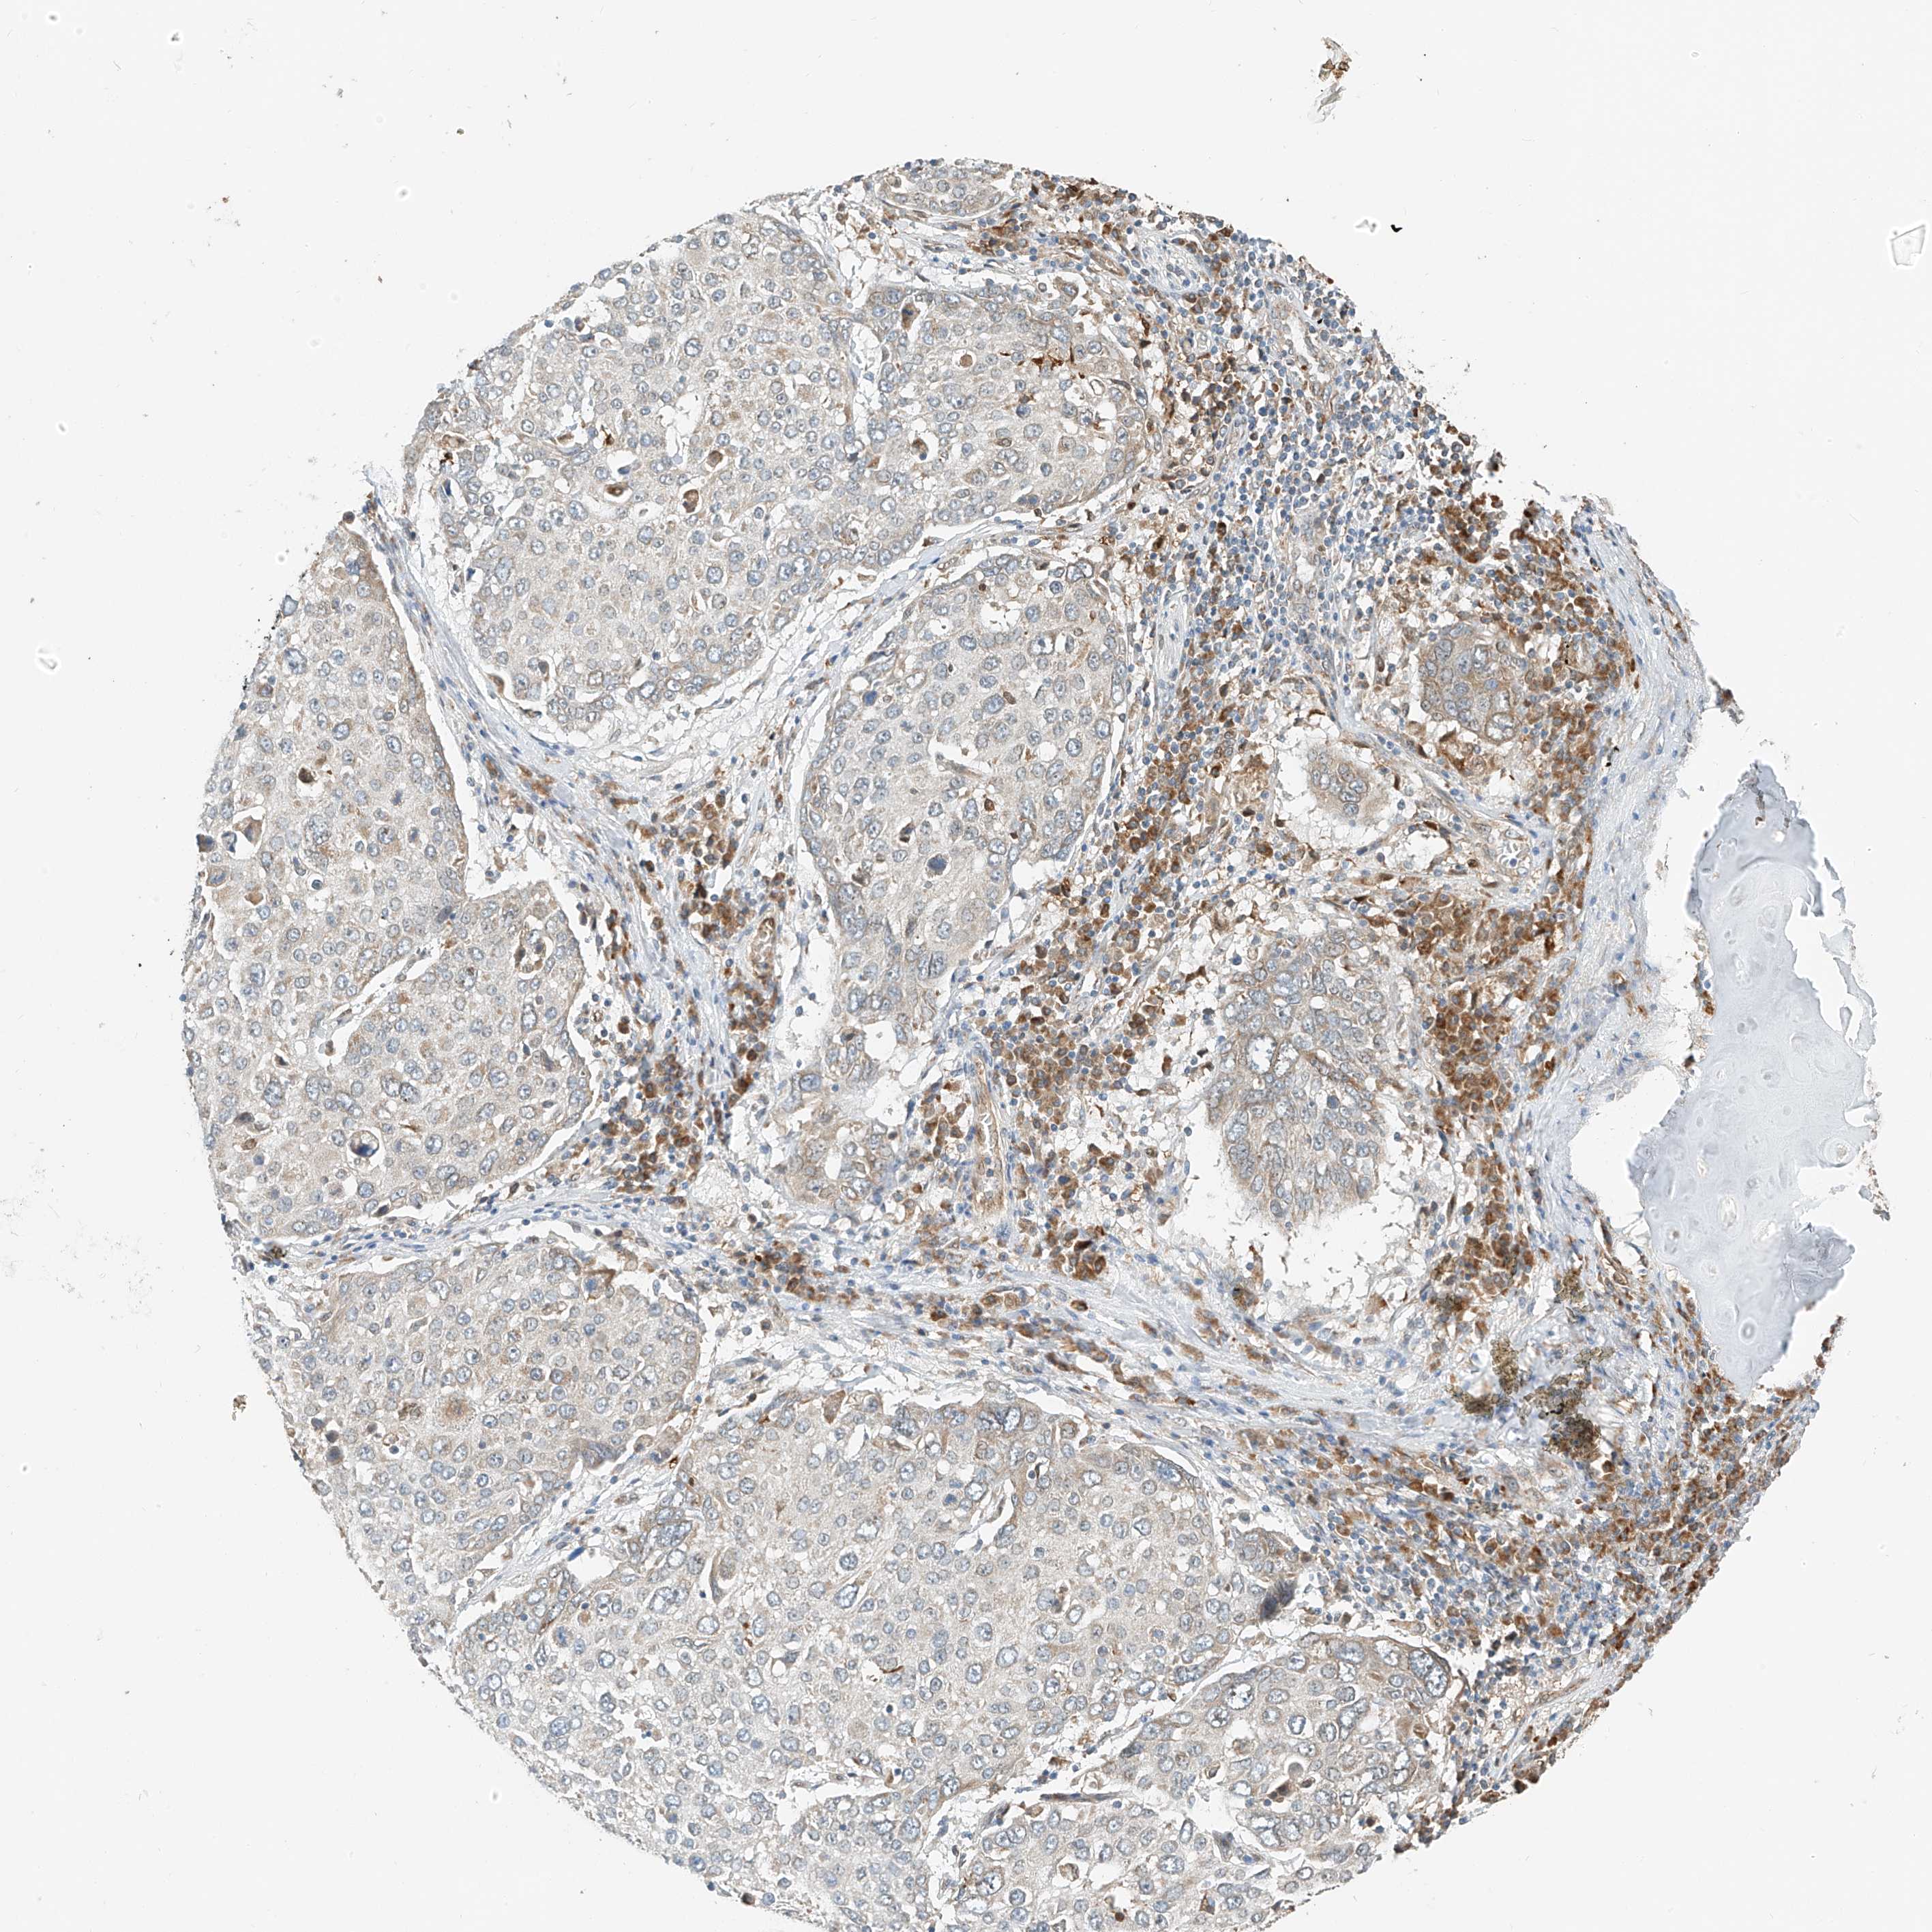

CANCER LUNG CANCER Show tissue menu

LUAD TCGA LUAD VALIDATION LUSC TCGA LUSC VALIDATION PROTEIN LUAD CPTAC PROTEIN LUSC CPTAC PROTEIN EXPRESSION

ANTIBODIES

AND

VALIDATION